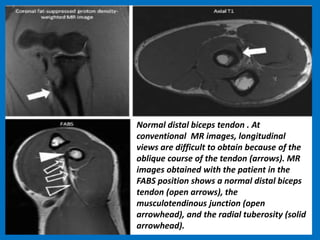

Normal distal biceps tendon . At

conventional MR images, longitudinal

views are difficult to obtain because of the

oblique course of the tendon (arrows). MR

images obtained with the patient in the

FABS position shows a normal distal biceps

tendon (open arrows), the

musculotendinous junction (open

arrowhead), and the radial tuberosity (solid

arrowhead).